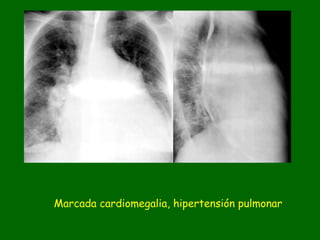

Marcada cardiomegalia, hipertensión pulmonar

Marcada cardiomegalia e incremento del flujo pulmonar